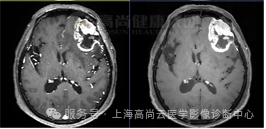

左额叶见不规则团块状异常信号影,边界欠清,大部分 T1WI 呈稍低、低信号,T2WI 及 T2 FLAIR 呈等稍高信号,内见点片状低信号,DWI 呈高信号,相应区域 ADC 呈稍低信号,ADC 值约 0.793 ×10-3 mm2/s,最大横截面大小约 44 mm×55 mm,病灶后部 T1WI 呈低信号,T2WI 呈高低混杂信号,FLAIR 呈稍低等混杂信号,SWI 呈明显低信号,DWI 以低信号为主,病灶周围见大片水肿信号影环绕,邻近侧脑室明显受压,左额部中线结构略右偏,增强后病灶呈明显不均匀强化,内可见不规则无强化坏死区,强化区域灌注扫描 CBF 增高,MRS 显示局部 Cho 峰明显升高,NAA 峰明显升高,Cho/NAA 比值约 87.02,出现 Lip 峰及 LAC 峰。3D T1WI 增强显示左侧额叶病灶邻近脑膜增厚强化;另外右侧颞窝底部可见小条状强化灶。

高级别胶质瘤(4 级)